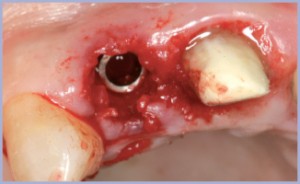

Un breve alesaggio con le frese dedicate ha consentito di adeguare le pareti dell’alveolo post-estrattivo all’impianto Exacone® prescelto, diametro 4,1×14 mm (figg. 4, 5, 6).

L’impianto è stato posizionato circa 2 mm sottocresta per assicurare una buona estetica in previsione del rimodellamento osseo verticale.

Un simile posizionamento è reso sicuro dal micro- gap medio all’interfaccia impianto-moncone inferiore a 1µm, tipico della connessione Exacone®: ciò limita al minimo il passaggio di batteri ed esotossine ed elimina i micro-movimenti, permettendo ai tessuti di interpretare il complesso impianto-sovrastruttura come un pezzo unico.

L’impianto è stato chiuso con un tappo di guarigione Standard diametro 4,1 GH 5; dopo l’inconamento la cavità esagonale è stata sigillata con del Cavit (3M Espe) (figg. 7, 8) per evitare un ristagno di placca e batteri durante il periodo di guarigione.

La mucosa è stata accollata al tappo con due punti di sutura staccati in seta.